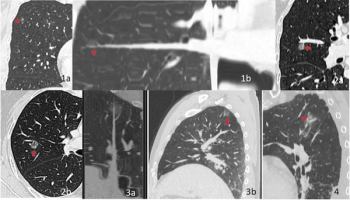

The cLung-RADS v2022 model offered a greater than 16 percent increase in the AUC in comparison to Lung-RADS 1.0 and Lung-RADS v2022 systems for predicting the invasiveness of pure ground-glass nodules.